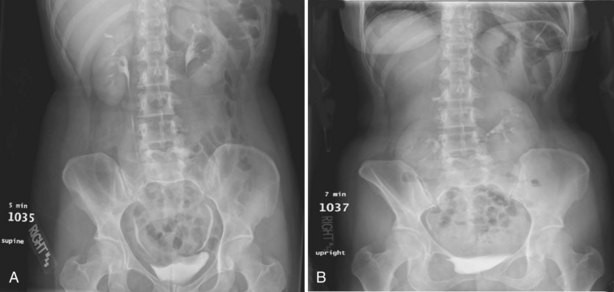

Upright films may be helpful in certain situations. In the rare case of suspected symptomatic renal ptosis, IVU can be particularly helpful (Fig. 4–3). Supine films are compared with upright films to measure the degree of ptosis. Such a comparison cannot be made with MRI or CT. In the case of calyceal stones or milk of calcium stones, layering of the contrast can be helpful to evaluate the anatomy of the calyx harboring the stones.

Figure 4–3 Intravenous excretory urogram (IVU) in a 40-year-old female with the complaint of a mobile mass in the right lower quadrant with standing associated with bilateral flank and back pain that resolved in the supine position. A, Supine IVU shows kidneys in the normal position, with normal ureters and proximal collecting systems. B, Standing film shows significant displacement of both kidneys with the right kidney moving onto the pelvis as described by the patient.